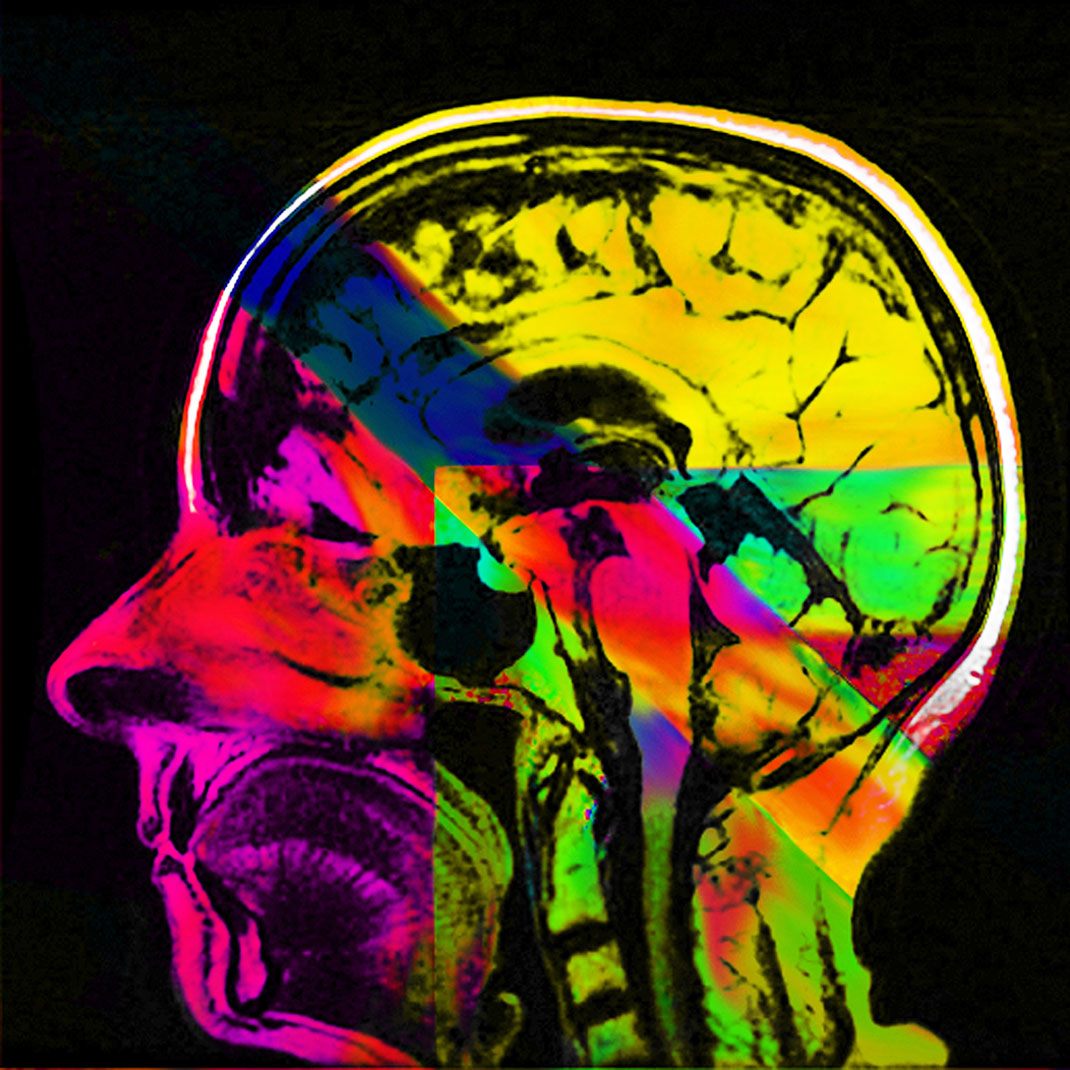

En 1991, elle découvre qu’elle est atteinte de sclérose en plaques. « J’étais en train de jouer avec mes enfants dans un parc. Je n’ai pas eu mal, je n’ai eu aucun signe de quoi que ce soit, j’ai juste découvert que je ne pouvais plus parler. La semaine suivante, les chirurgiens m’ont enlevé une partie du cerveau pour découvrir la source de mon aphasie. Le diagnostic était clair, j’étais atteinte de sclérose en plaques. A partir de ce moment-là, j’ai passé de nombreuses heures dans l’appareil IRM », explique-t-elle.

Elle trouve alors sa source d’inspiration dans sa maladie à travers ses IRMs. « Mes nombreux traitements m’ont donné envie de réinterpréter l’imagerie médicale. Les patients, souvent anxieux, ne voient que laideur et effroi dans les pixels noirs et gris des IRMs. J’ai alors ressenti le besoin vital de les utiliser pour montrer les merveilles et la beauté de nos cerveaux, y compris ceux souffrant d’une maladie. Je veux guérir les patients de la peur de regarder leurs IRMs », s’émeut Elizabeth.

En réutilisant ses scanners, Elizabeth Jameson cherche à insuffler des émotions et des sentiments dans la froideur technologique. Pour cela, elle utilise de nombreux supports : la peinture sur soie ou encore des impressions à partir de gravures sur cuivre ou sur plaque solaire. Ensuite, elle renforce la couleur de ses images grâce à de la peinture, des crayons ou du pastel sec. Le résultat offre une collection brillante, colorée, pleine d’émotion et de symbole.

Maintenant tétraplégique, Elizabeth crée avec l’aide d’un assistant. Selon elle, ses impressions ne sont pas qu’un moyen de faire la chronique des changements de son cerveau, qu’elle qualifie d’« organe le plus sacré ». Son travail est également un moyen de devenir plus familière avec ces changements, pour les rendre moins terrifiants. « Mon art est composé à 90 % de mon cerveau, tout simplement parce que je suis mon cerveau », conclut-elle.